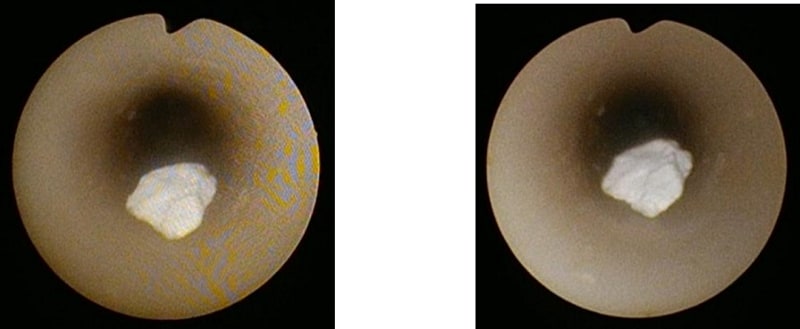

1.内視鏡画像の歪み軽減フィルターを搭載し、より精細な画像の提供を可能に

本製品は、画像の歪みを軽減させるフィルターを搭載しました。より精細な画像の提供を可能とし、質の高い観察をサポートします。

左:従来機種、右:OES ELITE ウレテロレノスコープ